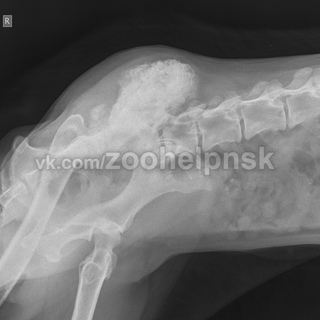

После удаления части кости на ее место устанавливается индивидуально подобранный имплантат (специальная титановая пластина с повышенной степенью прочности) в сочетании с костным цементом, который заполняет недостающую часть кости (Рис. 11). Именно имплантаты в последующем и будут являться опорой для кости. Подбор имплантов очень важен так как они должны обладать достаточной прочностью и поэтому наши врачи одни из первых в России стали использовать современные LCP имплантаты (блокируемые пластины и блокируемые гвозди) (Рис.

12, 13, 14).

При поражении локтевой кости мы также впервые в России использовали блокируемый штифт (гвоздь). Данная техника позволяет уже через 24 часа после операции полноценно пользоваться конечностью (Рис. 15).

Рис. 15. Рентген грудной конечности пациента с остеосаркомой средней трети локтевой кости (область разрушения кости отмечена желтыми стрелками).

Компьютерная томография грудных конечностей этого же пациента.

3D моделирование: Компьютерная томография грудных конечностей с сочетанной КТ-биопсией кости.